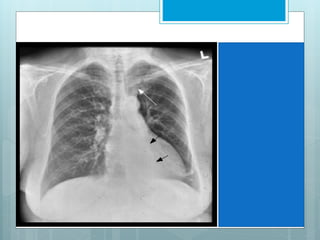

RLL Collapse

 Another indirect sign is vascular nodular sign, due to

compensatory hyperinflation of upper lobe.

 Radiographically seen as "hair-pin" turning of vessels &

"too-many nodules" along cardiac margin, which are end-on

vessels.